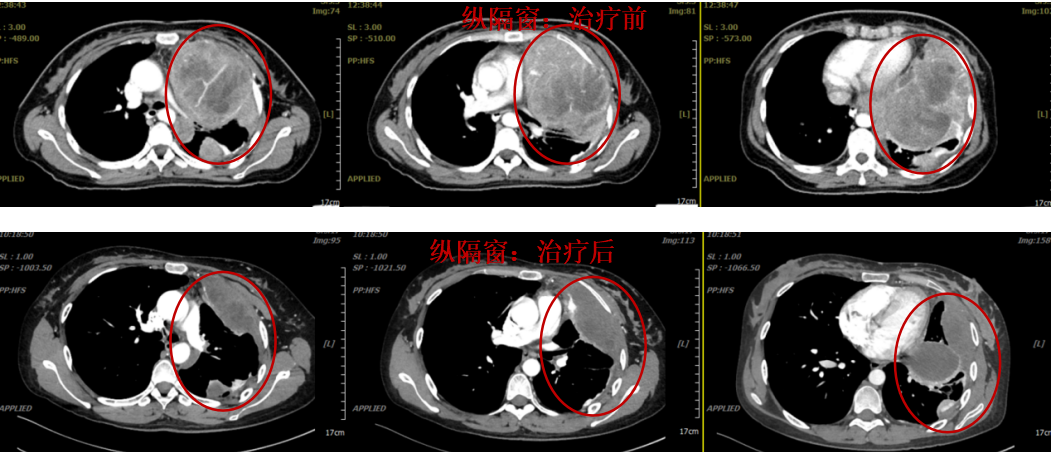

Mediastinal window:

Before treatment, the tumor occupied the entire left thoracic cavity with a significant mass effect, and the heart was markedly compressed.

After treatment, the left lung re-expanded, most of the tumor disappeared, and the heart returned to its normal position.